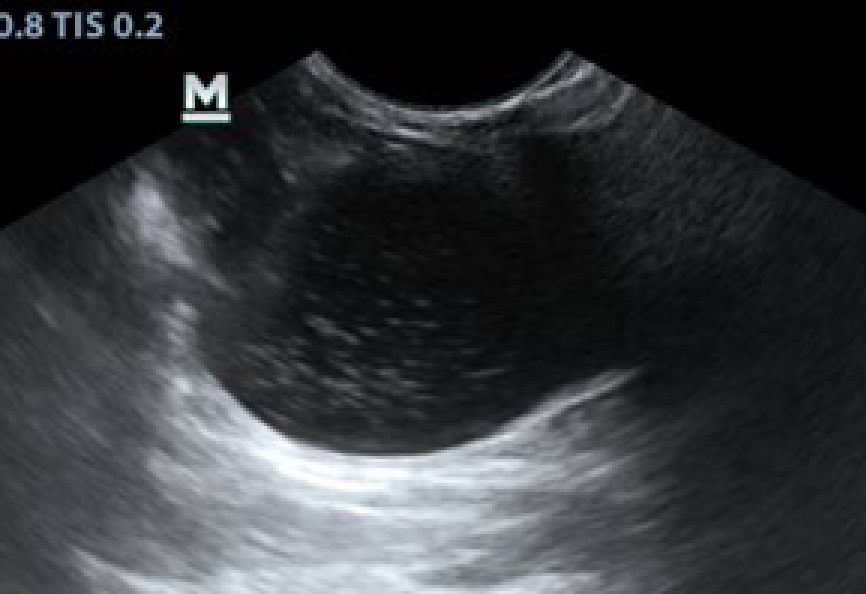

Ультразвуковое исследование (УЗИ). У животных с диагнозами «цистит» и «уроцистит» выявляли следующие изменения: мочевой пузырь лоцировался топографически правильно, имел овоидную форму. Его объем варьировался в зависимости от степени наполненности, при частичной обструкции мочеиспускательного канала объем остаточной мочи был увеличен. Содержимое пузыря анэхогенной природы, нередко с наличием мелкодисперсной взвеси различной эхогенности (рис. 3), стенка утолщена (рис. 4).